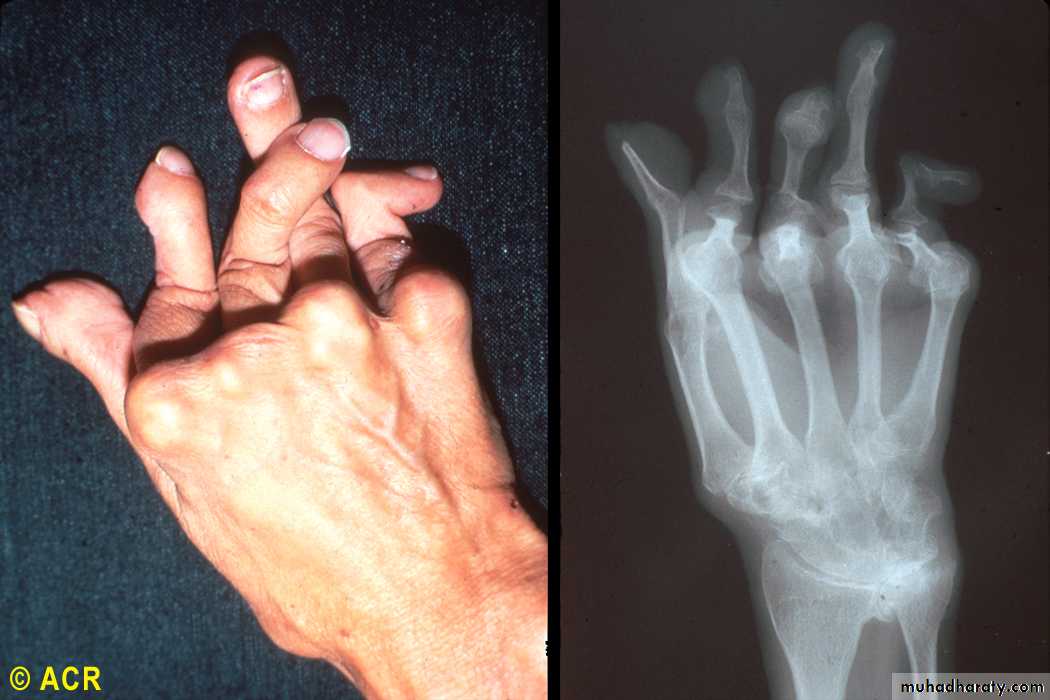

Rheumatoid arthritis: swan-neck and boutonnière deformity, hand

Nonreducible flexion at the PIP joint with concomitant hyperextension of the DIP joint of the finger (boutonniere deformity, occurs as a consequence of synovitis with stretching of, or rupture of, the PIP joint through the central extensor tendon with concomitant volar displacement of the lateral bands.

Hyperextension at the PIP joint with flexion of the DIP joint (swan-neck deformity, may be initiated by disruption of the extensor tendon at the DIP joint with secondary shortening of the central extensor tendon and hyperextension of the PIP joint,

Rheumatoid arthritis: arthritis mutilans, hand (clinical and radiograph)

Rheumatoid Arthritis

24